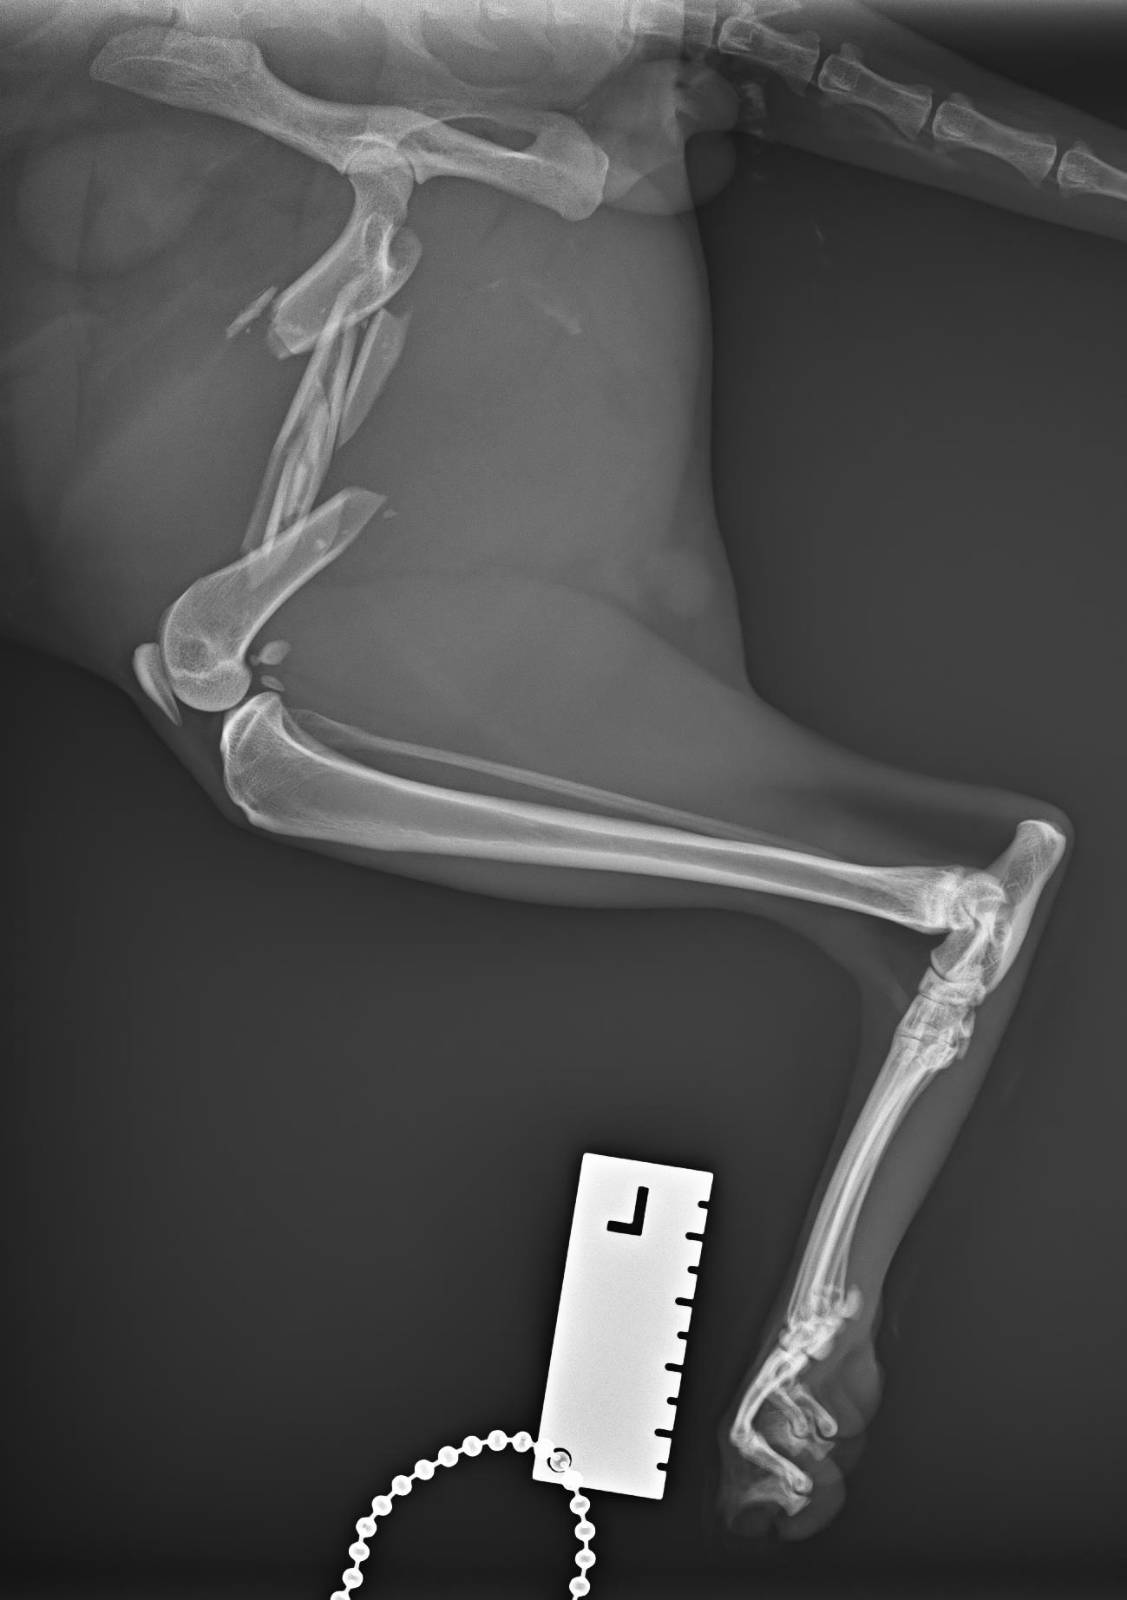

A couple weeks ago someone hurt Alastor. A blunt impact fractured his femur in 6 fragments, and the vet suggested that the most probable cause was another human intentionally hurting him.

Alastor had to get operated, stabilizing his broken bones with a needle and is now undergoing recuperation. He is now much better, but the surgery was costly and we’d greatly appreaciate any help covering the bills.